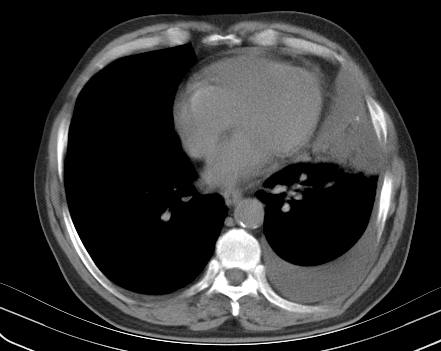

以下是引用老爱克斯新网客在2008-7-31 6:30:00的发言:[br]左肺上叶大片状病灶,左肺上叶支气管狭窄呈鼠尾状,左肺门增大,纵隔内见肿大淋巴结,左侧胸腔积液,余肺清晰。左肺中心型肺癌淋巴结转移,

以下是引用zjb在2008-7-31 6:32:00的发言:[br]左侧中心性肺癌 阻塞性肺炎 肺不张 胸腔积液 建议气管镜

以下是引用zjzjr在2008-7-31 8:45:00的发言:[br]考虑左侧中心性肺癌伴阻塞性肺炎,左肺上叶肺不张,纵隔淋巴结转移;左侧胸腔积液。建议行纤支镜检查。

以下是引用sdzyy在2008-7-31 8:47:00的发言:[br]病灶较治疗前有所进展,胸水增多, 左侧中心性肺癌 并 阻塞性肺炎 肺不张 胸腔积液 可能性大; 建议气管镜检查。 [br] [br]